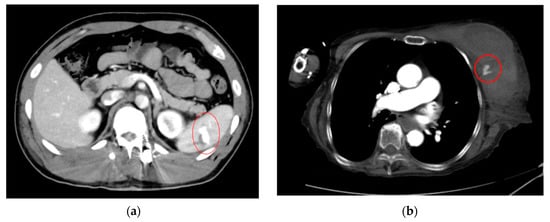

- AI for Image Analysis: AI-based image analysis algorithms can enhance the detection and diagnosis of extravasation events in imaging studies, such as ultrasound, MRI, and CT. These algorithms can automatically identify subtle signs of extravasation, assist healthcare providers in interpreting the imaging findings, and facilitate a timely intervention. This suggestion is subsequently extended as a separate discussion.